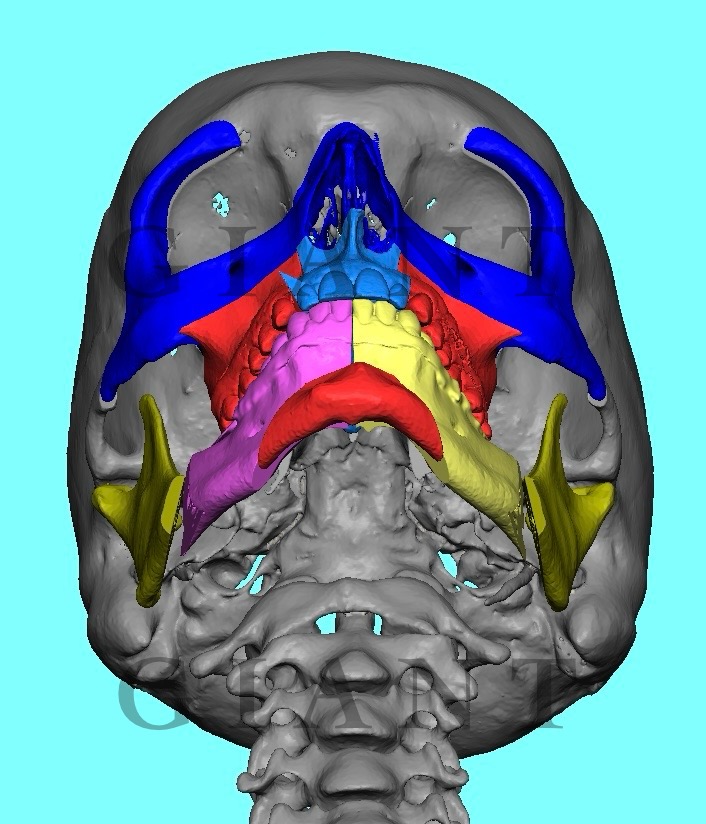

Yo @RealSurgerymax what your opinion on zso to widen face here’s example of eppley

IMG 3239

IMG 3240